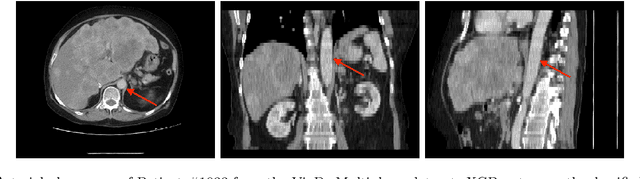

Abstract:Purpose: The purpose of this study is to harness the efficiency of a 2D foundation model to develop a robust phase classifier that is resilient to domain shifts. Materials and Methods: This retrospective study utilized three public datasets from separate institutions. A 2D foundation model was trained on the DeepLesion dataset (mean age: 51.2, s.d.: 17.6; 2398 males) to generate embeddings from 2D CT slices for downstream contrast phase classification. The classifier was trained on the VinDr Multiphase dataset and externally validated on the WAW-TACE dataset. The 2D model was also compared to three 3D supervised models. Results: On the VinDr dataset (146 male, 63 female, 56 unidentified), the model achieved near-perfect AUROC scores and F1 scores of 99.2%, 94.2%, and 93.1% for non-contrast, arterial, and venous phases, respectively. The `Other' category scored lower (F1: 73.4%) due to combining multiple contrast phases into one class. On the WAW-TACE dataset (mean age: 66.1, s.d.: 10.0; 185 males), the model showed strong performance with AUROCs of 91.0% and 85.6%, and F1 scores of 87.3% and 74.1% for non-contrast and arterial phases. Venous phase performance was lower, with AUROC and F1 scores of 81.7% and 70.2% respectively, due to label mismatches. Compared to 3D supervised models, the approach trained faster, performed as well or better, and showed greater robustness to domain shifts. Conclusion: The robustness of the 2D Foundation model may be potentially useful for automation of hanging protocols and data orchestration for clinical deployment of AI algorithms.